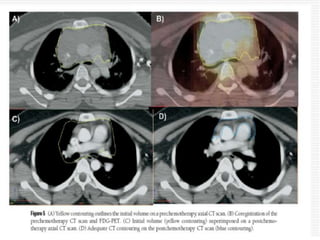

 The contouring process is as follows:

 1. The CT images of the pre chemotherapy PET/CT are used to

 2. The PET images of the pre chemotherapy PET/CT are used

PET as determined by FDG uptake

 3. The pre chemotherapy PET/CT is fused with the post

are imported to the planning CT images

 4. The post chemotherapy tissue volume, which contained the

other anatomic changes.

 The CTV

normal structures